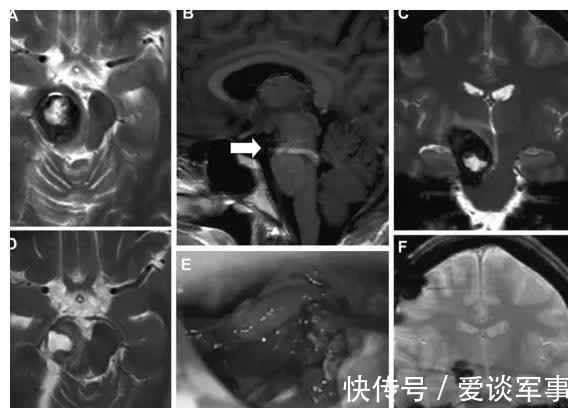

图2:患者1分娩后的术前MRI(A–C)、术中视图(D)和术后MRI(E和F):轴向(A)、矢状面(B)和冠状面(C)MRI平面显示脑干海绵状血管瘤病变的残余和较大的DVA(箭头,B)。术中观察(D)显示手术腔和海绵状血管瘤少部分残留(星号)。

祸兮福所倚,福兮祸所伏。一路磕磕绊绊,本以为可以一直幸福下去的陈女士,再次出现体征。分娩两个月后,陈女士出现左侧面部麻痹,经MRI证实脑桥切除腔再出血。与最初的图像相比,在脑桥区发现一个脑干海绵状血管瘤残余或复发,更多的是背侧和下方(图2)。T1核磁共振造影(考虑到胎儿安全,未在妊娠期间进行)显示竟是一个巨大的发育性静脉异常(DVA,一种先天性脑血管畸形)。